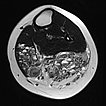

Axial T2-weighted MRI of the left lower leg shows multiple dilated, dysplastic veins in a venous malformation throughout the superficial flexor muscles. Slow flow causes stasis of the blood within the malformation with the formation of fluid-fluid levels. Almost the entire muscle consists of malformation and fatty tissue. Also visible is a large thrombus in a dilated, dysplastic vein.

The vascular channels are largely occluded on axial control MRI in T2-weighted images. However, after successful occlusion of the vascular channels, a black-and-white “salt-and-pepper” pattern typical of FAVA remains. This consists of adipose tissue (hyperintense) and connective tissue (hypointense).